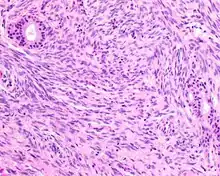

Smooth-muscle actin reaction in a biphenotypic sinonasal sarcoma

• Smooth-muscle actin or muscle-specific actin is seen in nearly all tumors, but a strong and diffuse reaction with SMA is seen in only about 50% of cases.

• No reactivity occurs with other tumor markers such as SOX10, myogenin, estrogen receptor, progesterone receptor, or keratins.